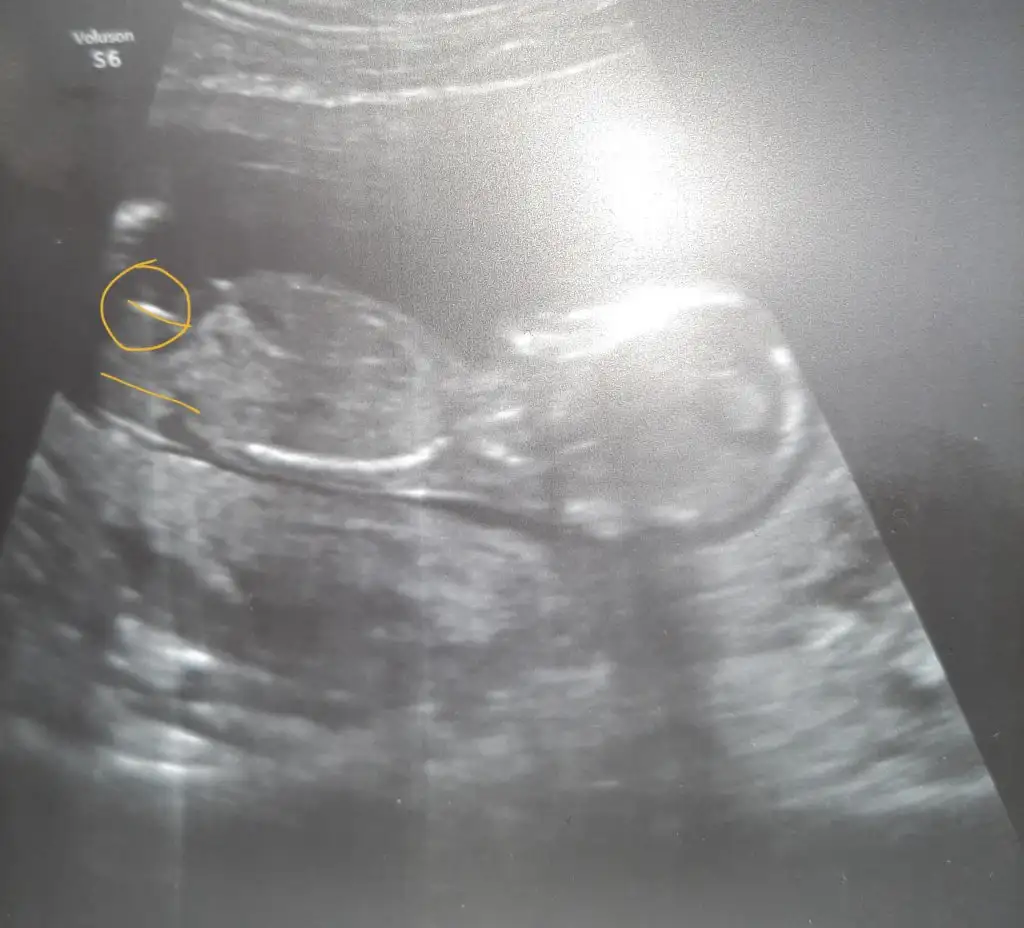

Yokki cnm sadece renkli varRenkli değil diğer USG varsa paylaşın burada nubu belli degil 11 12 13 haftalar olmalı

Nub çok uzun görüyor. Bence kızBide buna bakın isterseniz.

Kız13+0 haftalık olduk bize de lütfen yorum yaparmısınız

Erkek gibi sanki13+0 haftalık olduk bize de lütfen yorum yaparmısınız